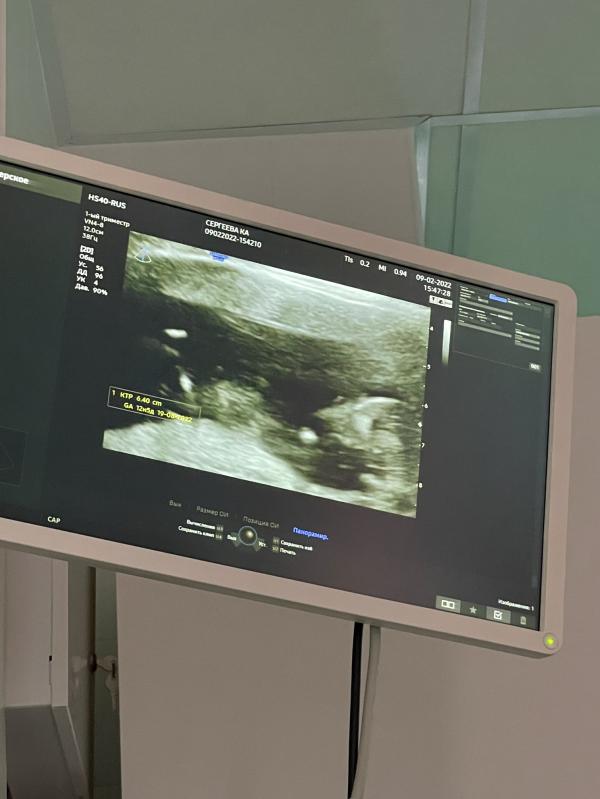

На память😍

Первый скрининг моей малышки💕